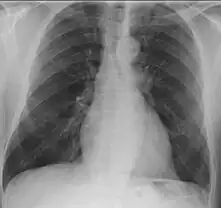

The left apical region is opacified in a case of granulomatosis with polyangiitis.

• Lungs: abnormal chest X-ray with:

• nodules,

• infiltrates or

• cavities